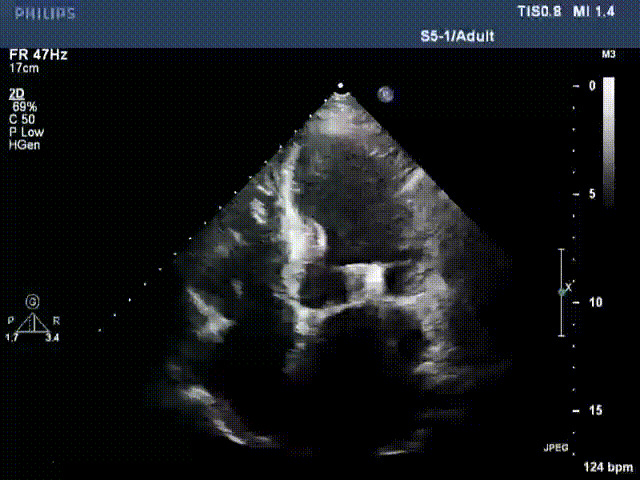

出院前隨訪超聲